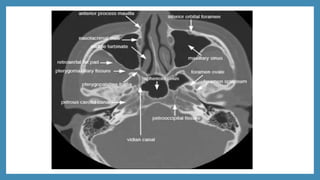

AXIAL CT

CT scan

 CT scans: Excellent views of the sinuses, best for osteomeatal

complex and ethmoidal disease

 “Limited CT Evaluation” – slice 3-4 mm

 CT navigation:

 A computer is used to identify the 3- dimensional location of a

probe tip placed within the patient's nose or sinuses..

 Improves anatomical identification and avoid damage to vital

neighbouring structures such as the brain and eyes.